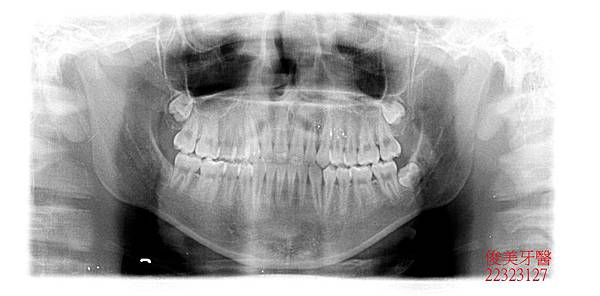

此位患者的咬合狀況為反咬,也就是所謂的戽斗咬合,家長於門診中表示,希望可以改善孩子的狀況。

在醫師的建議下已將門牙中間的多生牙做手術性拔除....並待傷口癒合..

患者的上顎犬齒也一直長不出來。

追蹤好幾年,目前下顎及上顎智齒皆已在適當時間拔除.....